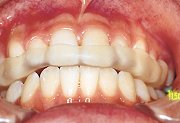

| まず、装着する上顎歯列をよく乾燥する。唾液で濡れていると、操作中にスプリントレジンLCが歯列から外れやすく、成形しにくい。 |